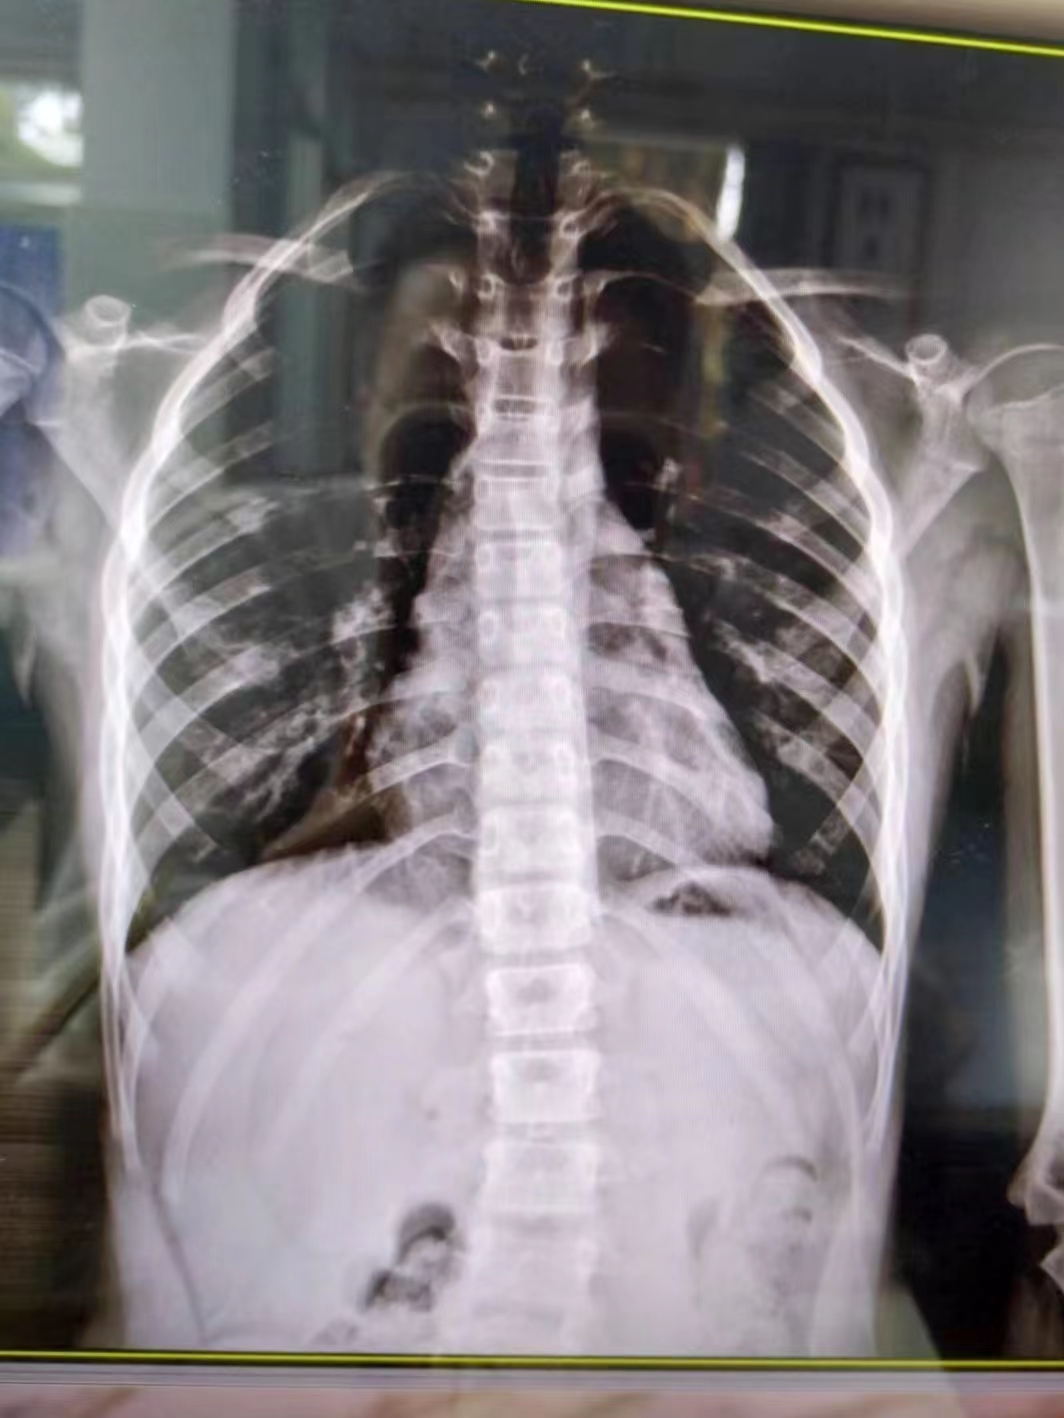

在康復(fù)醫(yī)學(xué)科,徐棟醫(yī)生通過X線片確認(rèn)小朋友患有脊柱側(cè)彎,“其實(shí)肉眼也可以看到小朋友的脊柱有彎曲弧度,家長的擔(dān)心是正確的?!?/p>

幸運(yùn)的是,由于媽媽發(fā)現(xiàn)及時(shí),小朋友的情況無需手術(shù)治療,經(jīng)過7次整脊手法按摩治療后,側(cè)彎明顯好轉(zhuǎn)。